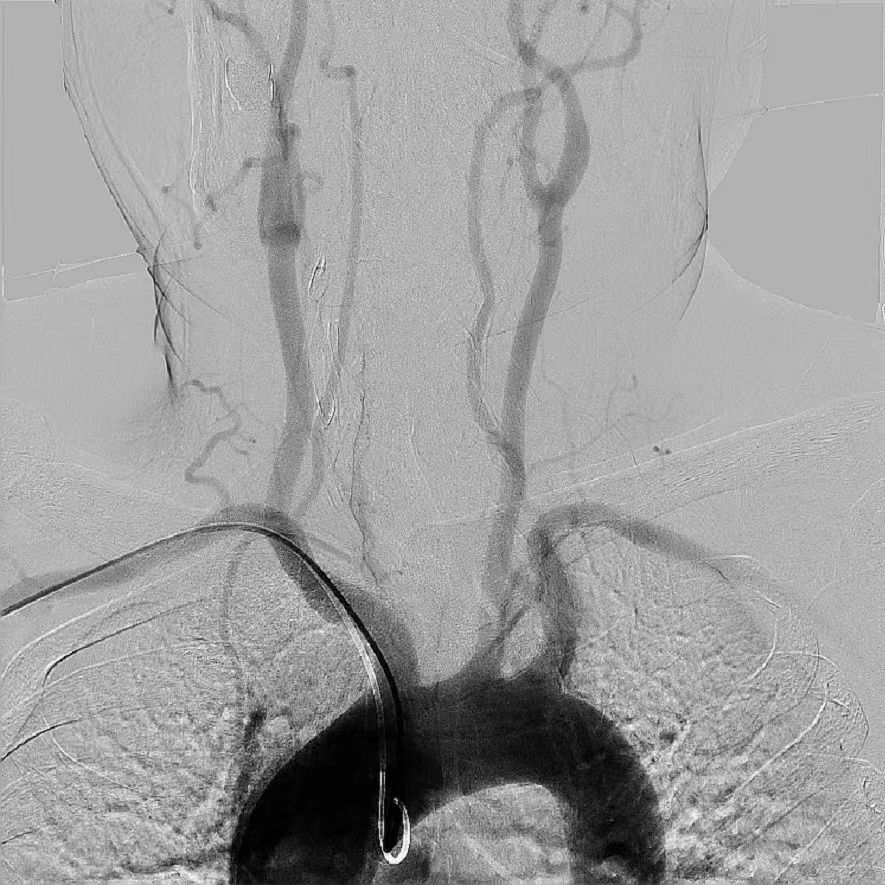

主動脈弓

左側頸動脈 / 右側頸動脈

左側椎動脈 / 右側椎動脈